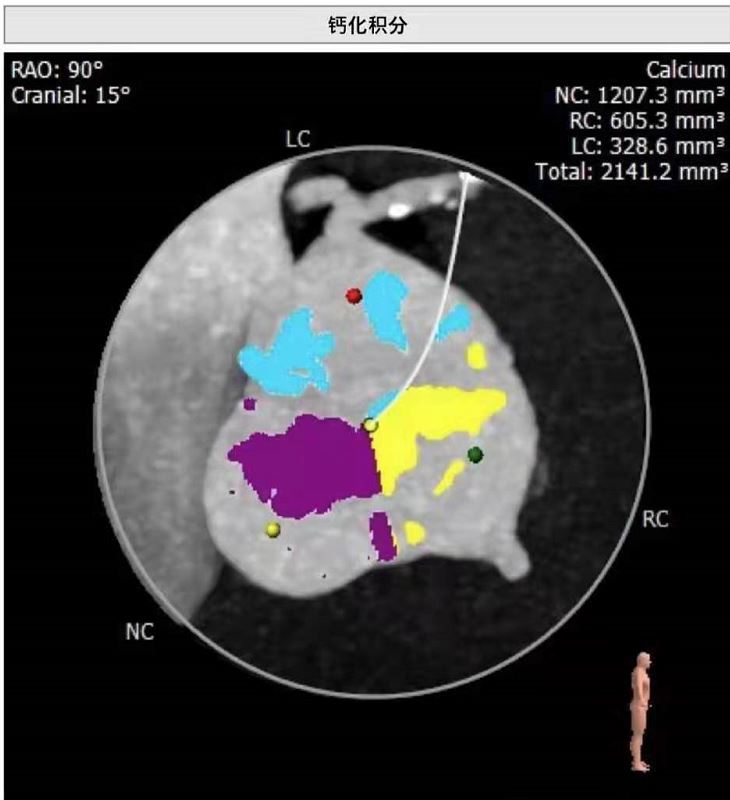

杨嗲嗲既往有“肺气肿”、“颈动脉粥样硬化”、 “胆囊结石”、 “前列腺增生”等病史。心脏彩超显示主动脉瓣钙化、重度狭窄并返流,冠脉影像显示冠状动脉病变也很严重。